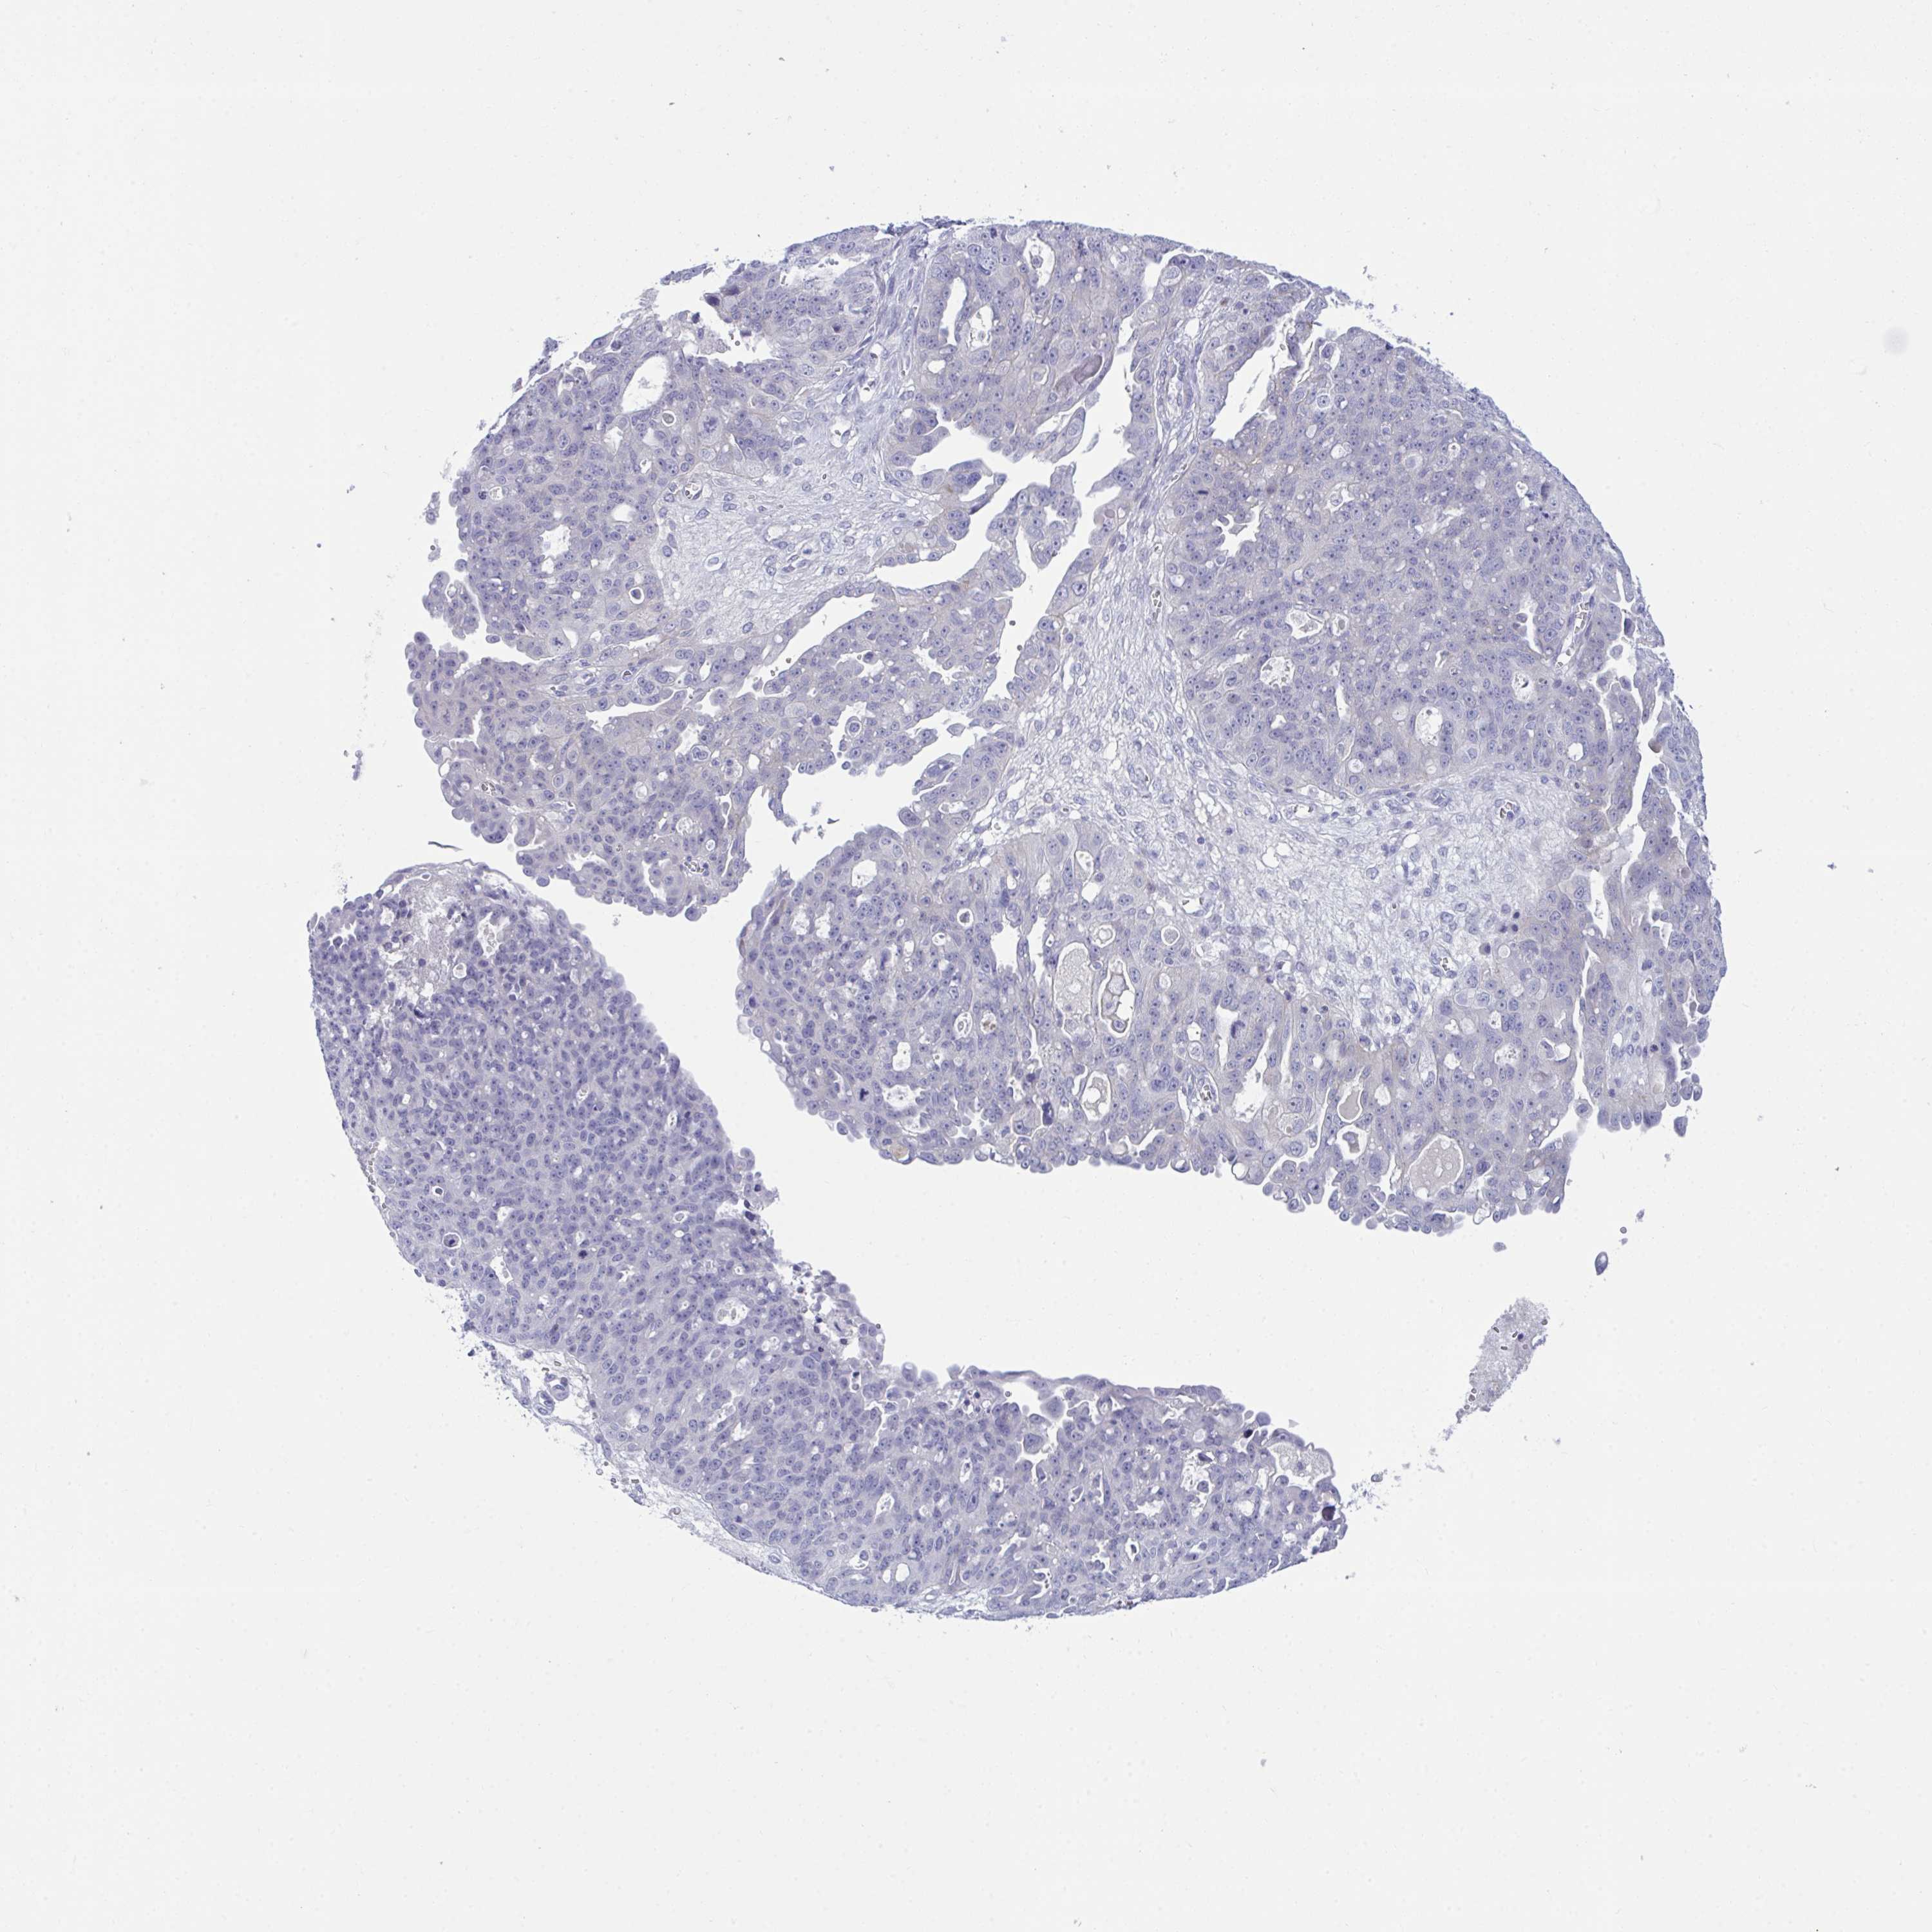

OVARIAN CANCER - Protein expressioni

A mouse-over function shows sample information and annotation data. Click on an image to view it in a full screen mode. Samples can be filtered based on level of antibody staining by selecting one or several of the following categories: high, medium, low and not detected. The assay and annotation is described here.

Note that samples used for immunohistochemistry by the Human Protein Atlas do not correspond to samples in the TCGA dataset.

Antibody stainingi

Antibody staining in the annotated cell types in the current human tissue is reported as not detected, low, medium, or high, based on conventional immunohistochemistry profiling in selected tissues. This score is based on the combination of the staining intensity and fraction of stained cells.

Each image is clickable and will lead to virtual microscopy that enables deeper exploration of all samples and also displays staining intensity scores, fraction scores and subcellular localization as well as patient and tissue information for each sample.

Antibody HPA056415

Staining

High

Medium

Low

Not detected

Intensity

Strong

Moderate

Weak

Negative

Quantity

>75%

75%-25%

<25%

None

Location

Nuclear

Cytoplasmic/membranous

Cytoplasmic/membranous,nuclear

Cystadenocarcinoma, serous, NOS

Cystadenocarcinoma, mucinous, NOS

Carcinoma, endometroid